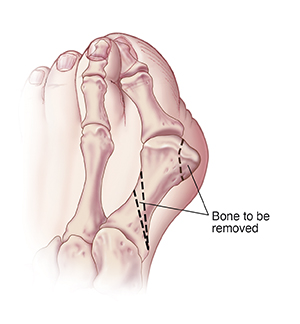

Base osteotomy

With this procedure, a wedge of bone is removed from the first metatarsal bone. This is farther back than in the head chevron osteotomy. The bone is moved closer to the second metatarsal bone. It's held together with screws or a plate. The bony bump is also removed. Your foot may be placed in a cast, shoe, or boot to heal correctly. You may be asked not to bear weight on this foot for a few weeks.